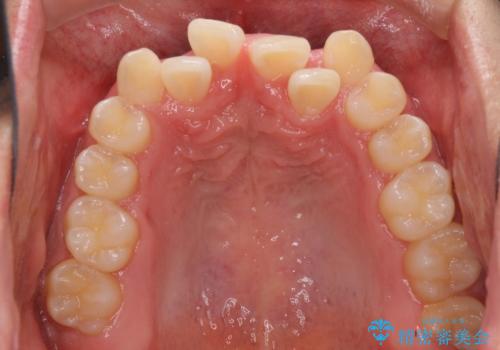

- 前歯のクロスバイトを気にして来院された患者様です。

美容専門の歯科医院を受診したところ、セラミックでの改善は無理と断られてしまったとのことでした。

歯がすり減って不揃いの形態となっていますが、まずは矯正治療によりクロスバイトを改善することとしました。

今後はすり減ってしまった歯の形をセラミッククラウンで改善したいとのことで、クロスバイトが改善し咬みやすくなった時点で装置を外すこととしました。

1年で治療を終えることができ、患者様には大変満足していただきました。